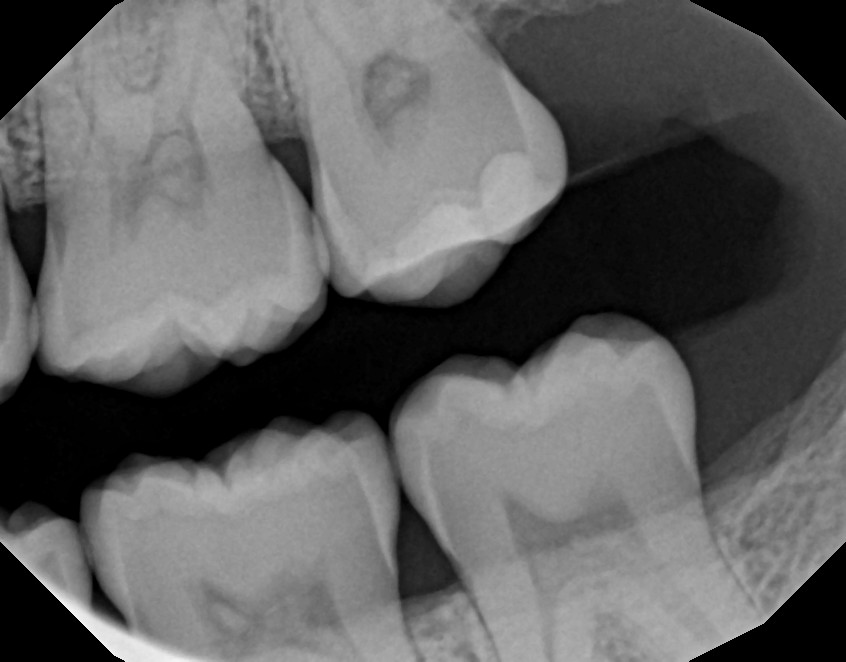

Treatment begins with an exam. The dentist or hygienist measures the spaces between the gums and teeth and looks for signs of inflammation. X-rays may be used to check bone levels.